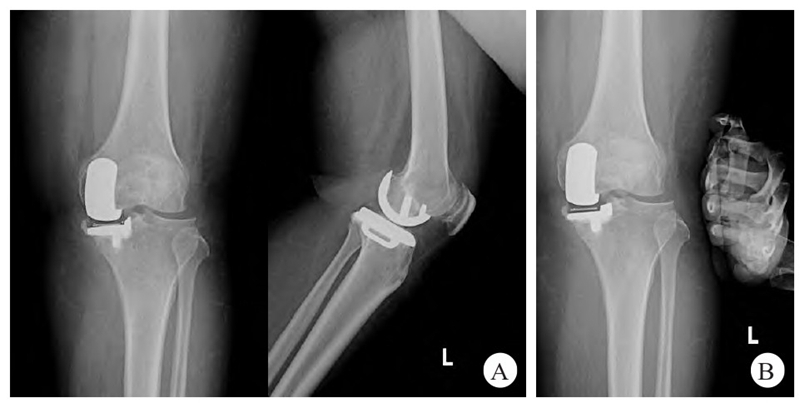

术后6周随访,患者双下肢可完全负重行走,右膝关节活动度0°~135°,左膝关节活动度0°~90°,左膝关节外翻试验(−),X线检查显示假体位置良好,膝关节外翻试验下进行X线检查,显示膝关节稳定(图3)。

图3 患者术后6 周左膝关节X线表现

A. 左膝关节正、侧位X线片可见假体位置良好;B. 膝关节外翻试验下左膝关节正位X线片显示膝关节内侧间隙未过度张开,内侧副韧带功能正常。